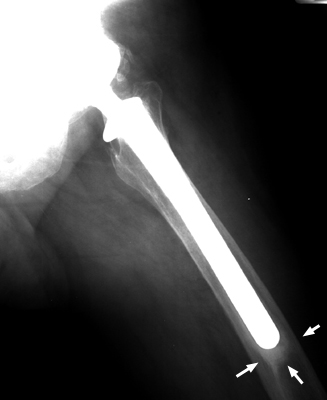

Diagnosis:Loosening prosthesis Discussion:Always associated with the presence of divergent radio-opaque lines, the pedestal sign is indicative of prosthetic loosening of the femoral stem in cementless total hip arthroplasty. The presence of radio-opaque lines within a radiolucent area, separated from the prosthetic tip by at least 2 mm, is defined as the "pedestal sign." References: